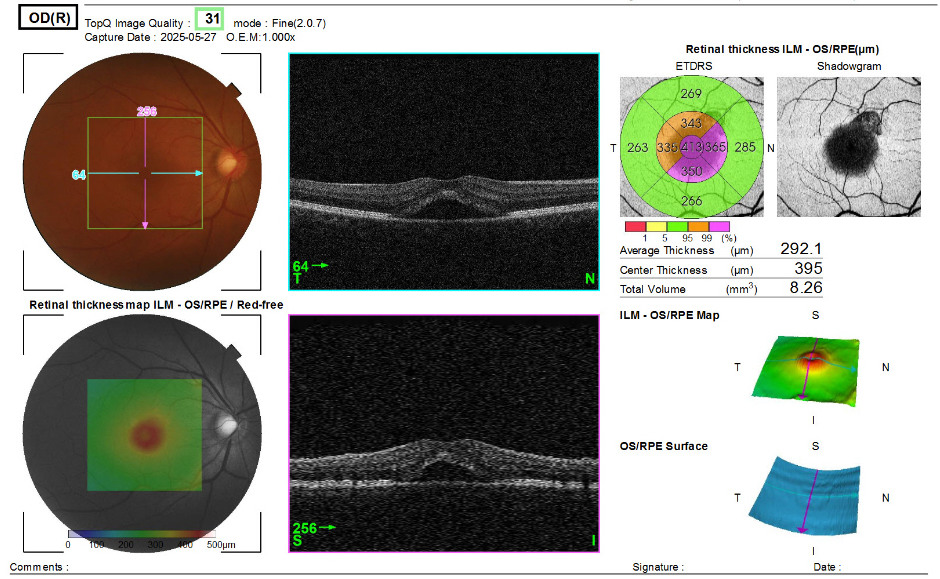

오른쪽 눈(OD: Oculus Dexter) 검사 결과

- 평균 망막 두께: 292.1μm

- 중심망막 두께: 395μm (정상 대비 현저히 증가 → 황반부종 의심)

- 총 망막 부피: 8.26 mm³

- ETDRS 망막 격자 분석:

- 중심 부위: 413μm

- 주변부: 대부분 330~365μm로 고르게 두꺼운 경향

- 단층 영상(B-scan): 중심 부위에 볼록한 돔 모양과 망막 내 수분 축적 소견 → 망막 내 낭포성 변화(Cystic edema) 가능성

- 3D 맵: 중심부에 국소적으로 돌출된 황반 영역 확인 가능

판단: 황반 중심부에 국소적 부종이 뚜렷하게 관찰되며, 이는 황반부종(Macular Edema) 또는 중심장액성맥락망막병증(CSC) 가능성을 시사합니다. 당뇨, 혈관폐쇄 병력 유무 확인 필요.